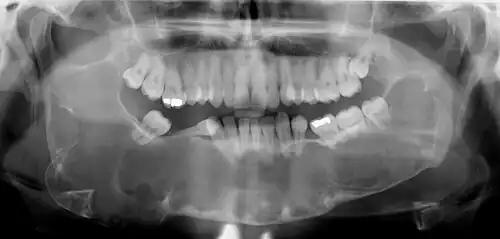

Radiographs of odontogenic keratocysts show well-defined radiolucent areas with rounded or scalloped margins which are well demarcated.[13] These areas can be multilocular or unilocular. The growth pattern of the lesion is very characteristic from which a diagnosis can be made as there is growth and spread both forward and backward along the medullary cavity with little expansion. No resorption of teeth or inferior dental canal and minimal displacement of teeth is seen. Due to lack of expansion of the odontogenic keratocyst, the lesion can be very large when radiographically discovered.[10]